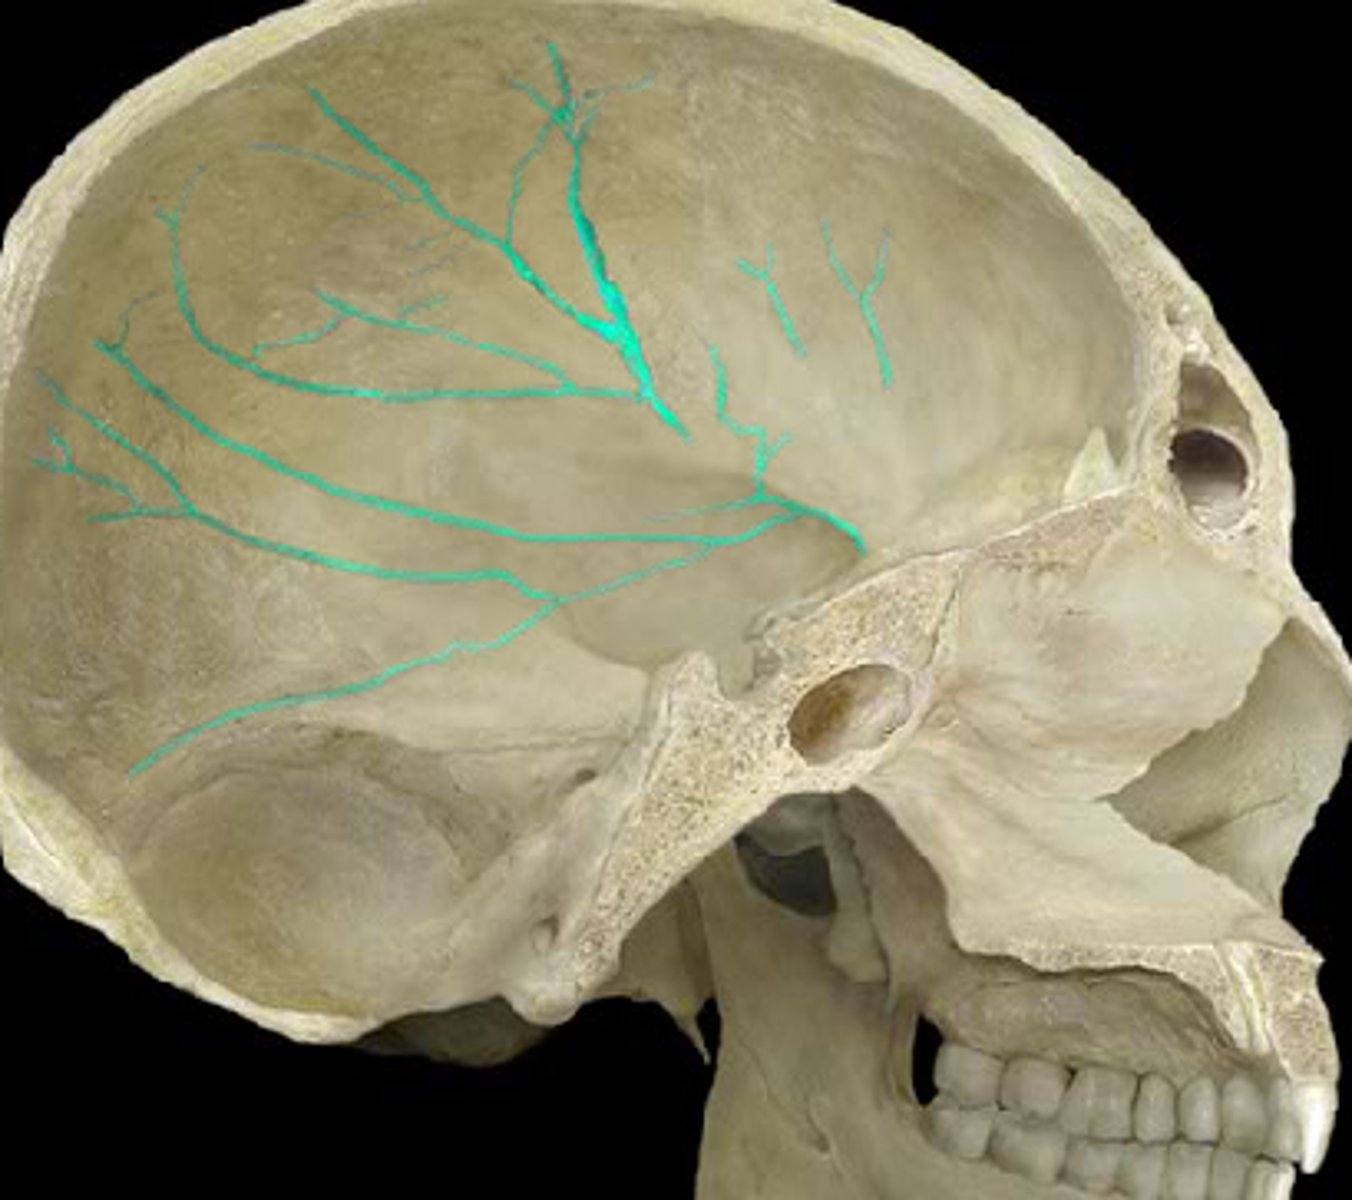

foramen spinosum of sphenoid bone

surrounded by grooves for middle meningeal vessels and meningeal branch of mandibular nerve

grooves for middle meningeal vessels of parietal bones